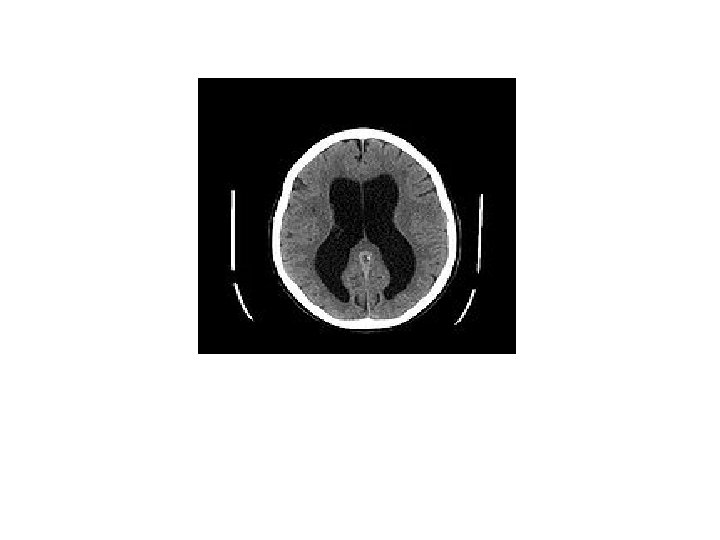

Hydrocephalus • Increased amount of CSF in the ventricles of the brain • Increase CSF pressure • Ventricular dilatation • Due to imbalance between production and absorption of CSF

Hydrocephalus…. • Hydrocephalus Ex Vacuo – also called normal pressure hydrocephalus – Ventricular dilatation due to cerebral atrophy – No increase in CSF pressure

Hydrocephalus…. • Diagnosis – Serial measurement of head circumference (An increase in head circumference more than cm in every 2 weeks in first 3 months of lifediagnostic) -USG head -CT/ MRI of head 1